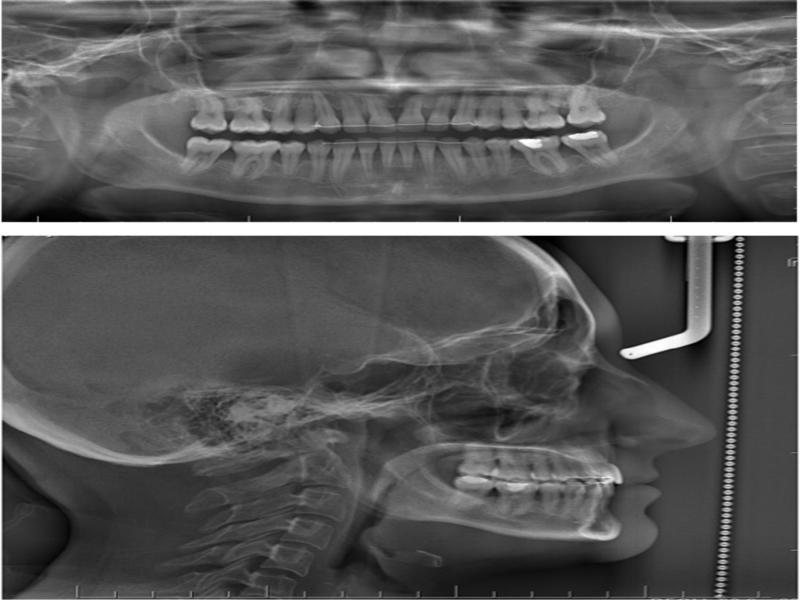

Figure 4.

Figure 5.